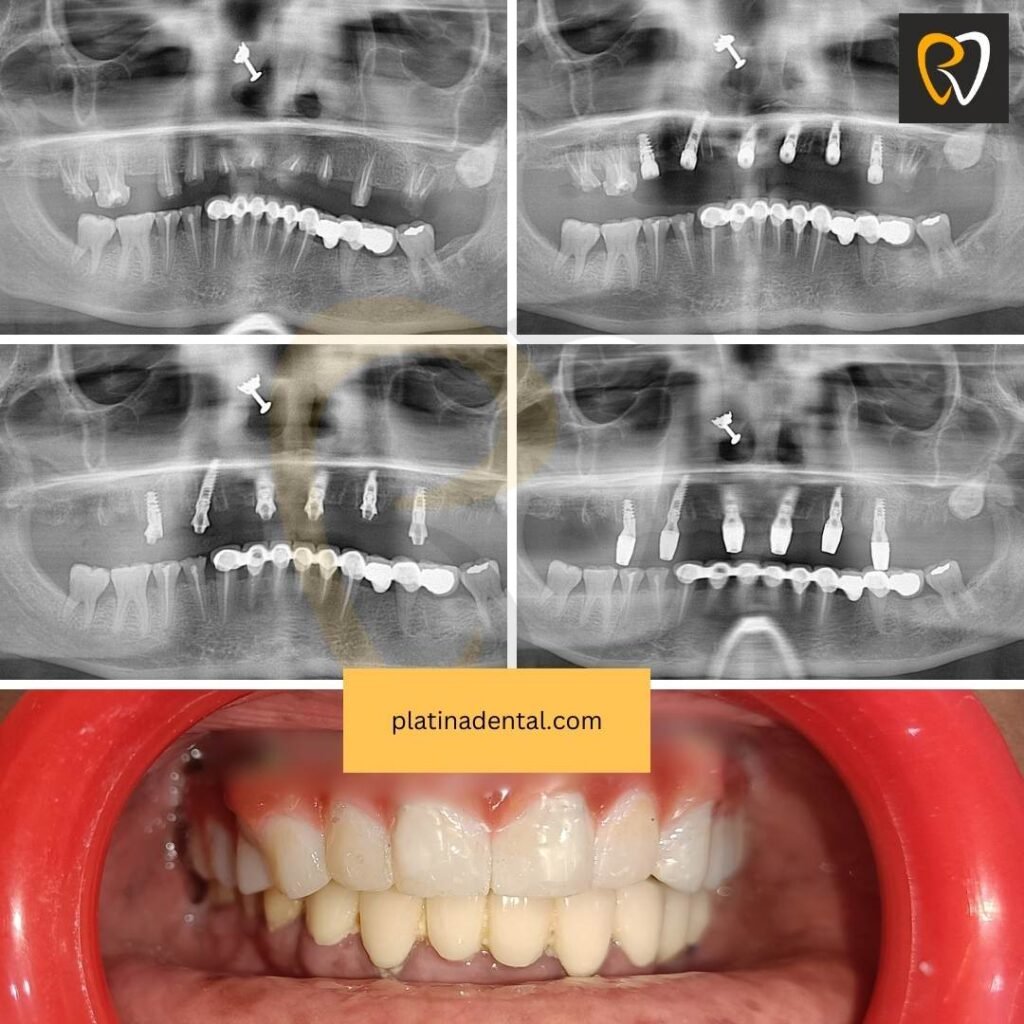

Full Mouth Restoration Transformation

Full mouth implant rehabilitation provides:

- Complete smile makeover

- Improved facial support

- Stable permanent teeth

What Makes a Successful Result?

Dr. Swetha explains:

“A successful before and after result is not just visual — it must function naturally and remain healthy long-term.”